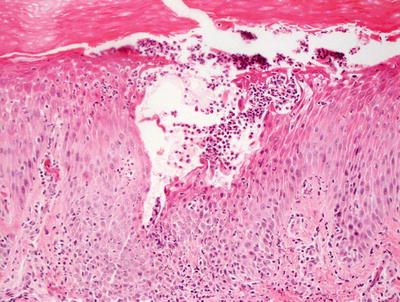

3.1.2 Histology

The histologic findings of acropustulosis of infancy are not specific, but characteristic of this entity. The epidermis has foci of spongiosis with microvesiculation [2] (Fig. 3.3). Neutrophilic abscesses are present within the vesicles (Fig. 3.4). Acute lesions do not have parakeratosis, although this is a common finding in more established lesions. Less commonly, eosinophils may be present within the microvesicles [3].

Fig. 3.4

Subcorneal neutrophilic clusters are present in acropustulosis of infancy